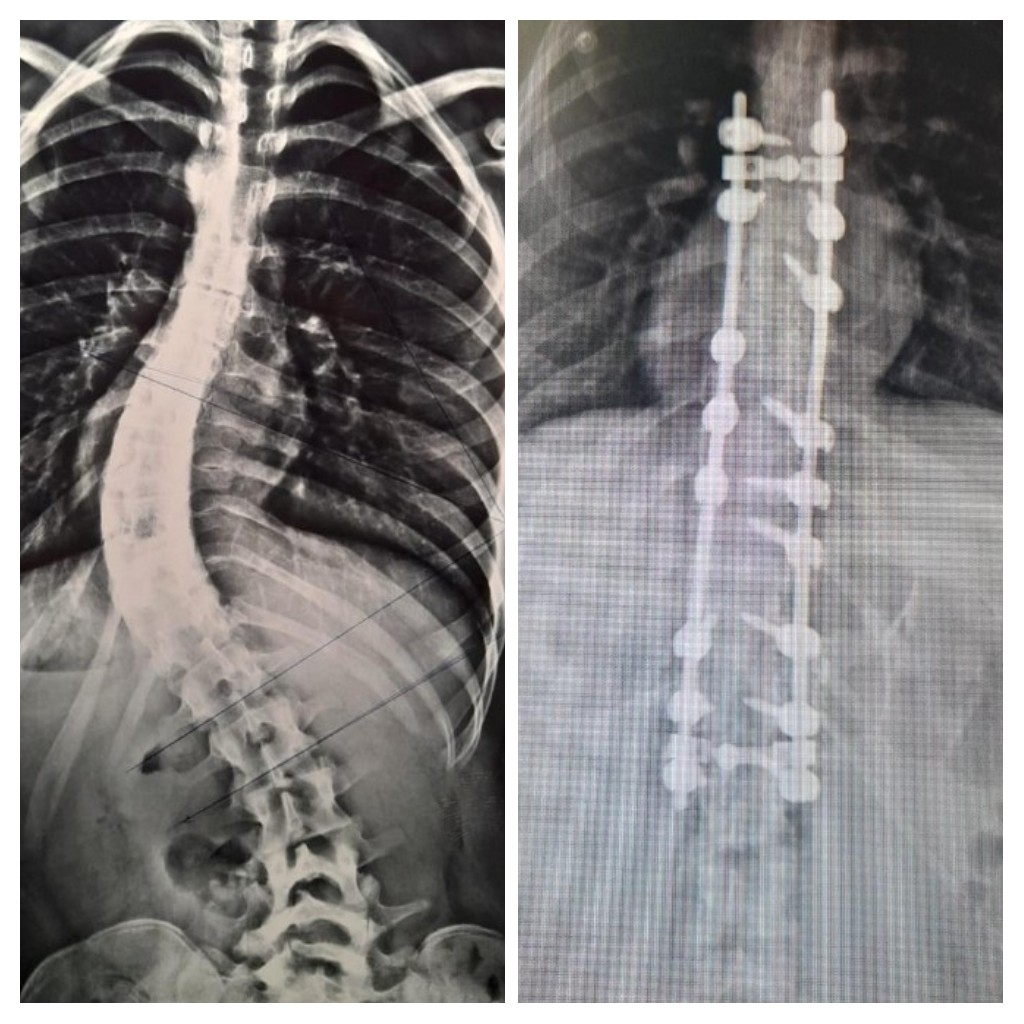

En el Hospital Interzonal San Juan Bautista, de manera exitosa, se realizó días atrás una nueva cirugía para corrección de columna vertebral en una joven paciente que presentaba escoliosis dorsolumbar grave.

En un abordaje integral y colaborativo entre los hospitales San Juan Bautista y el de Niños Eva Perón, un especializado equipo traumatológico, dio intervención a una paciente de 17 años con malformación congénita, que había iniciado su tratamiento en el nosocomio infantil y que finalmente pudo ser operada en el de atención adulta.

En la cirugía, que tuvo una duración de más de 4 horas de quirófano, se logró la reducción de la deformación dorsolumbar mediante la colocación de barras y tornillos pediculares. Los Traumatólogos que estuvieron a cargo fueron Nicolás Flores Kanter y Pablo Ovejero -este último en colaboración por parte del Hospital de Niños-; con la anestesista, Dra. Adriana Bustos, y los instrumentadores Aldo Espilocin y Claudia Sánchez.